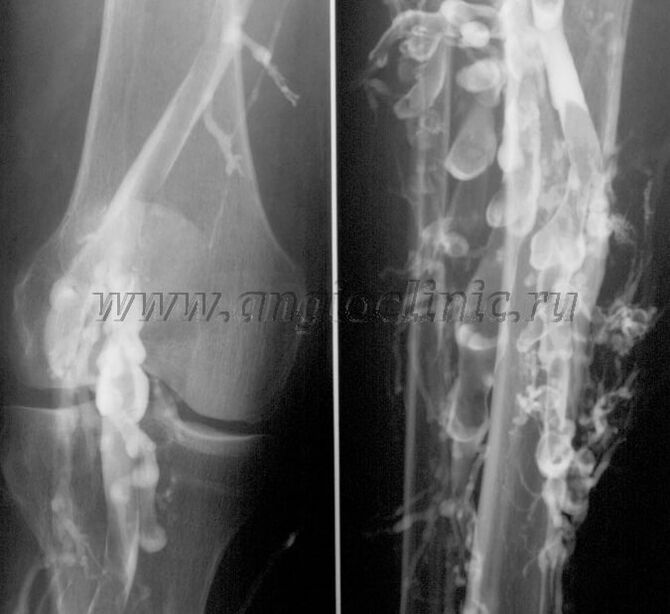

Contrast venography

Usually, an ultrasound scan is sufficient for a full diagnosis of venous pathology, but in some cases it is necessary to study the relationship between the state of the deep and superficial venous systems, especially in cases of recurrent varicose veins and secondary varicose veins.

To solve this problem, a contrast X-ray examination is used.The saphenous vein is punctured and contrast is administered.The movement of the contrast is observed on the monitor of the X-ray machine, and all necessary tests and projections are carried out.Currently, venography for varicose veins is used very rarely.